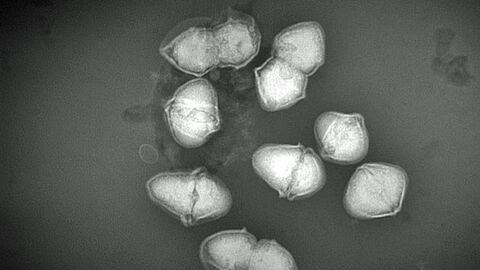

In zwei aufeinanderfolgenden Jahren wurden bei einer Gruppe Chaco-Pekaris Erkrankungen, auch mit Todesfolge, beobachtet. Betroffen waren vor allem junge Tiere im ersten Lebensjahr, die eitrige Infektionen der oberen und unteren Atemwege zeigten. Als Auslöser der ernsten Atemwegserkrankungen wurde ein bisher unbekannter bakterieller Erreger nachgewiesen [ Abb. 2]. Diese Bakterienart aus der Familie der Streptokokken konnte nun näher charakterisiert und taxonomisch beschrieben werden. Die neue Art wurde nach ihrer Wirtsspezies als Streptococcus catagoni sp. nov. benannt (Abb. 2) [3, 4].

Speziesbeschreibungen sind wissenschaftlich aufwändig, da eine Vielzahl an Eigenschaften und Daten über das Bakterium zusammengetragen werden müssen. Dies wurde nur durch die gute und vertrauensvolle Zusammenarbeit der beteiligten Institutionen möglich, zu der auch Experten aus zwei Instituten der Justus-Liebig-Universität Gießen, dem Robert-Koch-Institut in Berlin und dem Nationalen Referenzzentrum für Streptokokken am Universitätsklinikum Aachen gehörten. Wie bereits mehrfach in den letzten Jahren ergänzte die Expertise des CVUA Stuttgart in der identifizierenden Spektroskopie und der Elektronenmikroskopie die Arbeiten an den Streptokokken der Zootiere [Abb. 3].

Elektronenmikroskopische Abbildung des neu beschriebenen Bakteriums Streptococcus catagoni

Abb. 3: Elektronenmikroskopische Abbildung des neu beschriebenen Bakteriums Streptococcus catagoni